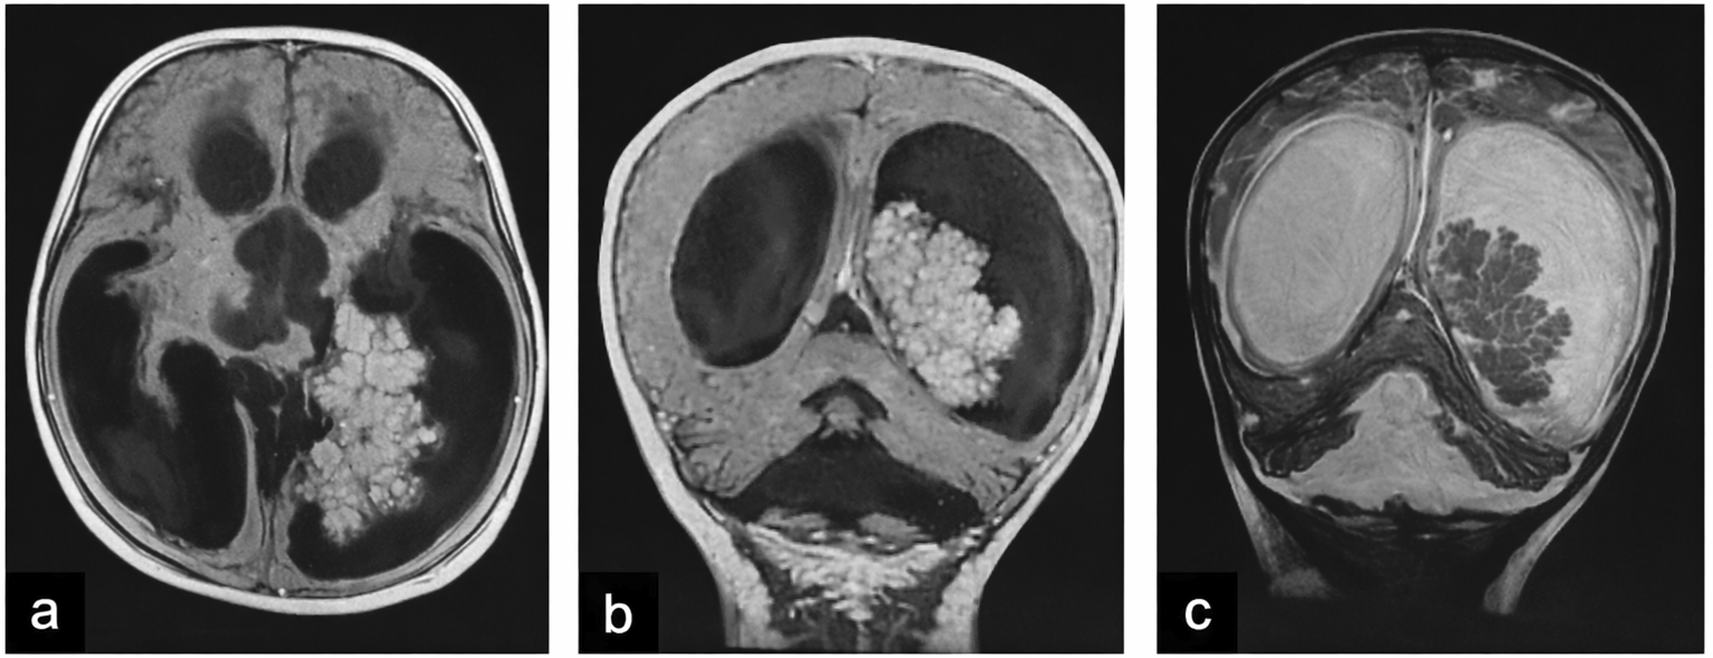

| 1 (CPP) | 28 F | Occipital headache, nausea, diplopia; cerebellar signs, CN V & VI deficits | 4th ventricle to CPA, 6×6 cm lesion, cystic + solid, heterogeneous enhancement, triventricular hydrocephalus (Figure 1) |

| 2 (CPP) | 2.8 F | Holocranial headache, projectile vomiting; clinically normal | Left occipital horn of the lateral ventricle, 5×4.7×3.8 cm, isodense, homogeneous enhancement, quadriventricular hydrocephalus (Figure 2) |

Tumors were located in the lateral ventricles in five cases (Figure 1), the third ventricle in one case, and the fourth ventricle with extension to the cerebellopontine angle (CPA) in one case (Figure 2). CT imaging (performed in six patients) showed lobulated intraventricular masses that were iso- to hyperdense with homogeneous enhancement in CPPs, frequently associated with hydrocephalus. CPCs appeared heterogeneously hyperdense with intense enhancement and intratumoral calcifications in two of three cases.

MRI (performed in five patients) demonstrated variable signal characteristics. CPPs were typically well-circumscribed and intensely enhancing, while CPCs appeared heterogeneous (Figure 3), with areas of calcification, hemorrhage, and parenchymal invasion. Hydrocephalus was present in the majority of cases ( Table 1).